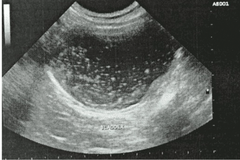

Chúng tôi đưa ra dịch vụ siêu âm và thông rửa bàng quang cho mèo để sớm giải quyết các vấn đề sỏi bàng quang một cách sớm nhất. Tránh để bị tắc tiểu mới đi chữa thì rất tốn kém và nguy hiểm đến tính mạng của mèo.